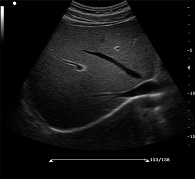

? ?● PHI脈沖反相組織諧波成像+頻率復(fù)合技術(shù)

? ? ? ?保證良好穿透力的同時(shí)獲得更加細(xì)膩的二維圖像

? ?● 空間復(fù)合成像技術(shù)

? ? ? ?通過(guò)多個(gè)角度圖像復(fù)合減弱單一圖像偽像,提高信噪比

? ?● 斑點(diǎn)噪聲抑制技術(shù)

? ? ? ?消除二維圖像斑點(diǎn)噪聲,顯著提高圖像信噪比